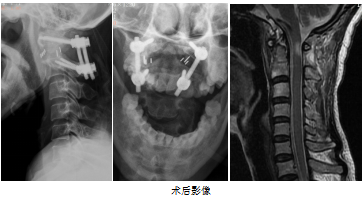

手術(shù)當(dāng)天,在陳贊的帶領(lǐng)指導(dǎo)下,莆田學(xué)院附屬醫(yī)院微創(chuàng)脊柱外科手術(shù)團(tuán)隊通過顯微鏡輔助,成功為林女士施行“頸后路顯微鏡下寰樞椎復(fù)位、側(cè)塊關(guān)節(jié)融合術(shù)”。手術(shù)歷時約1.5個小時,術(shù)后林女士恢復(fù)良好,第二天就能下床獨立行走。

莆田學(xué)院附屬醫(yī)院微創(chuàng)脊柱外科主任戴建輝教授介紹說,林女士是一名寰樞椎脫位伴不全癱患者,像這樣的病例,常規(guī)手術(shù)風(fēng)險大,而且術(shù)后融合失敗率較高。寰樞椎關(guān)節(jié)融合術(shù)融合率高,是治療寰樞椎脫位的一個重要補充。今后,莆田學(xué)院附屬醫(yī)院微創(chuàng)脊柱外科團(tuán)隊將運用推廣好該技術(shù),造福更多的患者。(來源:福建日報客戶端 記者 陳盛鐘 通訊員 嚴(yán)俊騰)